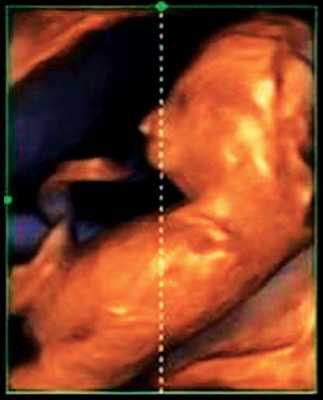

Революцией в пренатальной ультразвуковой диагностике явилось появление объемной эхографии, которая, обладая такими качествами, как неинвазивность, безопасность и возможность многократного применения у одной пациентки, имеет высокую информативность в исследовании анатомии плода и изучении его фенотипа. При применении различных режимов объемной эхографии абсолютно очевидно их преимущество по сравнению с обычным сканированием. Детально можно изучить лицо плода (рис. 1-4) в различные сроки беременности, начиная со сроков первого пренатального скрининга в 11-14 нед, конечности плода, причем не только их наличие и положение (рис. 5, 6), но и состояние и количество пальцев (рис. 7-9) как на руках, так и на ногах. Также можно изучить позвонки плода (рис. 10), состояние твердого нёба (рис. 11, 12), строение наружного уха (ушной раковины) (рис. 13), состояние основных швов черепа и родничков, исключая их преждевременное закрытие при кранисиностозах (рис. 14, 15).